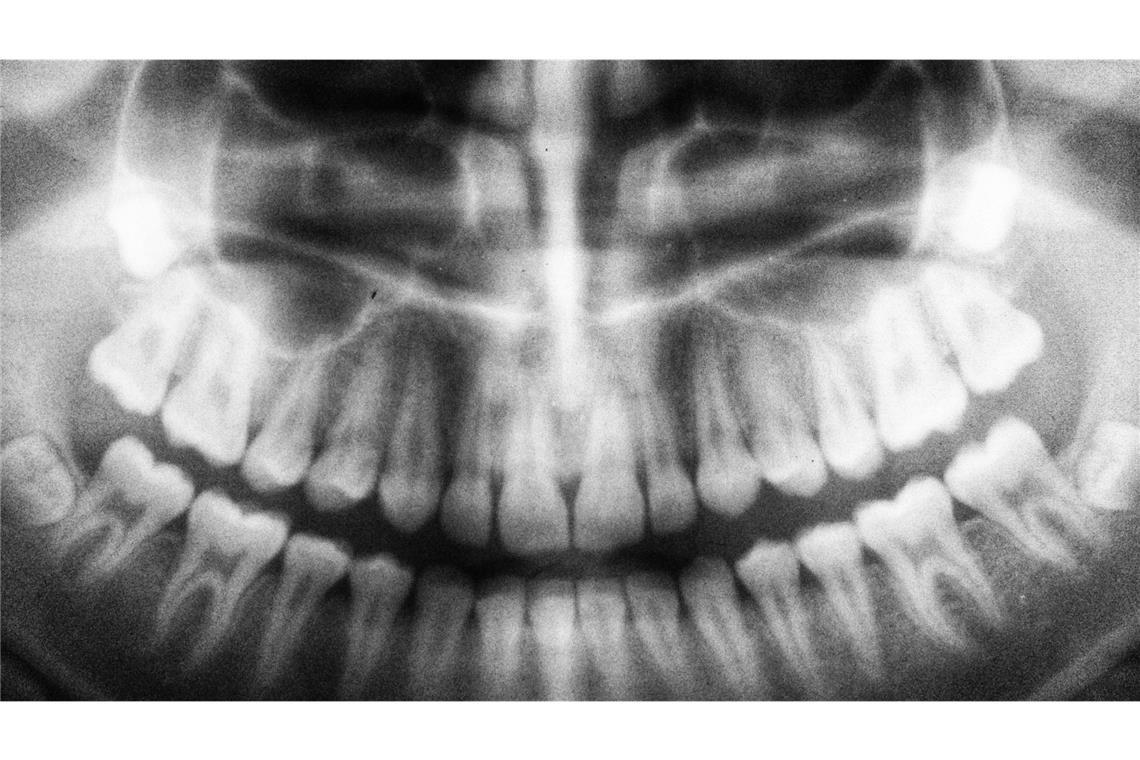

Doch nicht jeder Weisheitszahn erfordert eine direkte Reaktion. Es gibt Menschen, die mit allen Weisheitszähnen munter kauen können. Klarheit bringt meist ein Röntgenbild. „Wächst der Zahn gerade und bleibt unauffällig, kann er oft problemlos im Mund bleiben“, erläutert Blidschun. Anders sieht es aus, wenn wiederkehrende Entzündungen am Zahnfleisch im hinteren Kieferbereich auftreten, oder Schmerzen bestehen. „In diesen Fällen ist ein operativer Eingriff für Betroffene ratsam“, so die Expertin.